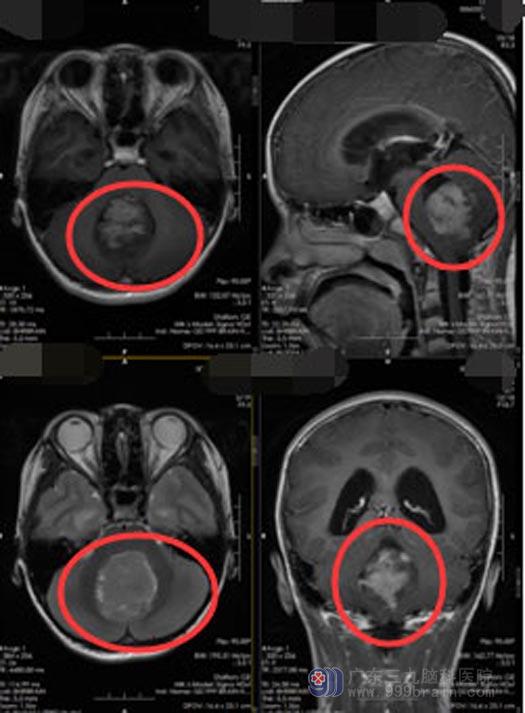

经过多方了解,小荧被父母带到了广东三九脑科医院神经外五科。入院后,主管医生对小荧进行了更全面的检查,结果和之前大体相同,提示:四脑室占位,初步判断是髓母细胞瘤,而且肿瘤体积较大,约46mm×41mm×40mm,出现了梗阻性脑积水,导致小荧频繁的头痛、呕吐。

很快,小莹接受了脑室外引流术;术后,颅高压的症状立刻得到了改善,她不再频繁的头痛、呕吐,身体状况也慢慢地得到了改善。随即接受了术前放化疗。结束放化疗后,按照之前制定的计划对小荧实施了第二次手术,手术很顺利,将肿瘤全部切除,术后小荧没有出现明显的并发症,术后影像检查未显示肿瘤残留。